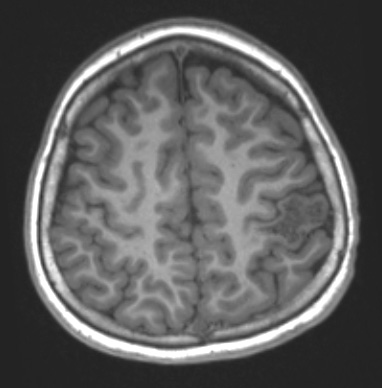

34A2 AVM, hybrid vessels (Case 34) T1NoC - Copy

This T1-weighted scan without contrast shows a hypointense malformation.